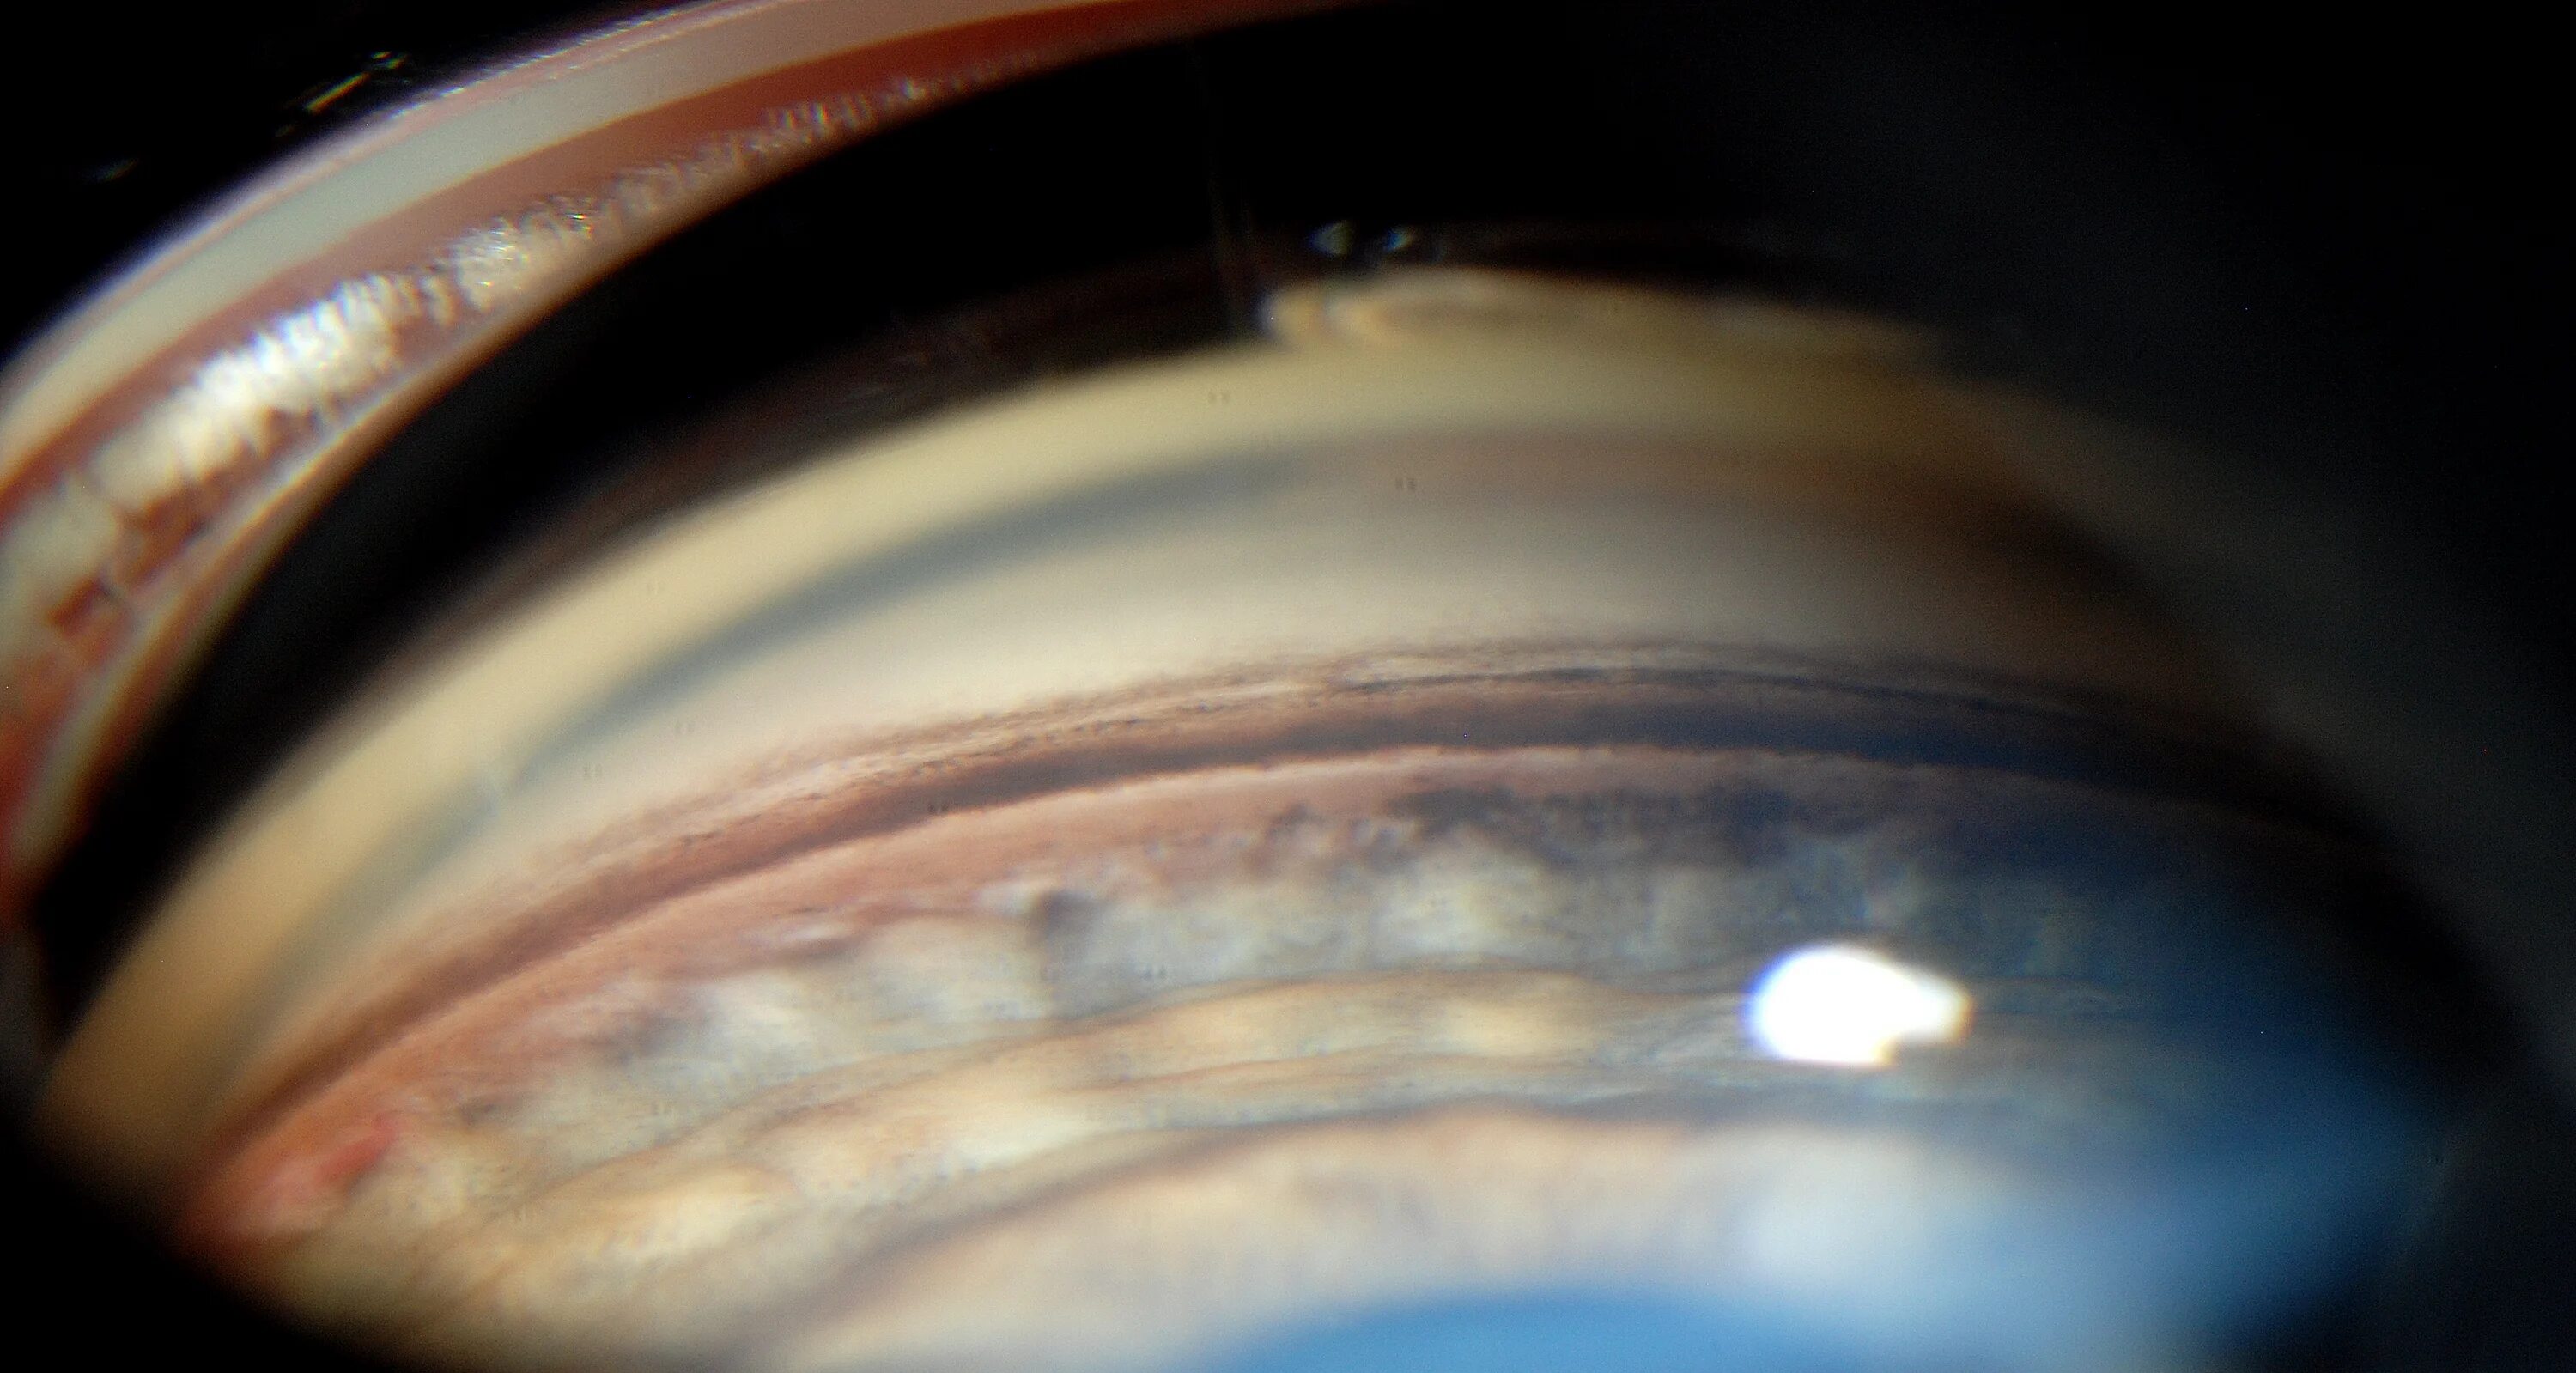

Функциональная желудочная диспепсия лечение. Основные симптомы болезней пищеварения. Синдром дисперсии. Пигментная глаукома гониоскопия. Клинические проявления кишечной диспепсии.

Синдром дисперсии. Бродильная диспепсия причины. Симптомы желудочной диспепсии. Корригированная дисперсия интервала qt. Гониоскопия экзогенная пигментация.

Синдром пигментной дисперсии. Дисперсия интервала qt. Пигментная глаукома гониоскопия. Синдром диспепсии. Гнилостная диспепсия симптомы.

Синдром дисперсии пигмента глаза. Дисперсия на интервале. Синдром дисперсии пигмента. Синдром дисперсии. Синдром пигментной дисперсии роговицы.